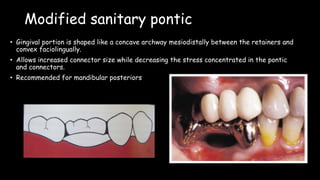

The document discusses pontic design for fixed dental prostheses. It covers pretreatment assessment of residual ridge contours, classifications of ridge deformities, surgical modification techniques, and ideal requirements for pontics. Pontic designs are classified based on their shape and materials. Factors in pontic selection include esthetics and oral hygiene. Common designs for anterior and posterior regions are described, including sanitary, ovate, and saddle pontics. Biological considerations for pontic design involve maintaining the residual ridge, abutment teeth, and supporting tissues.